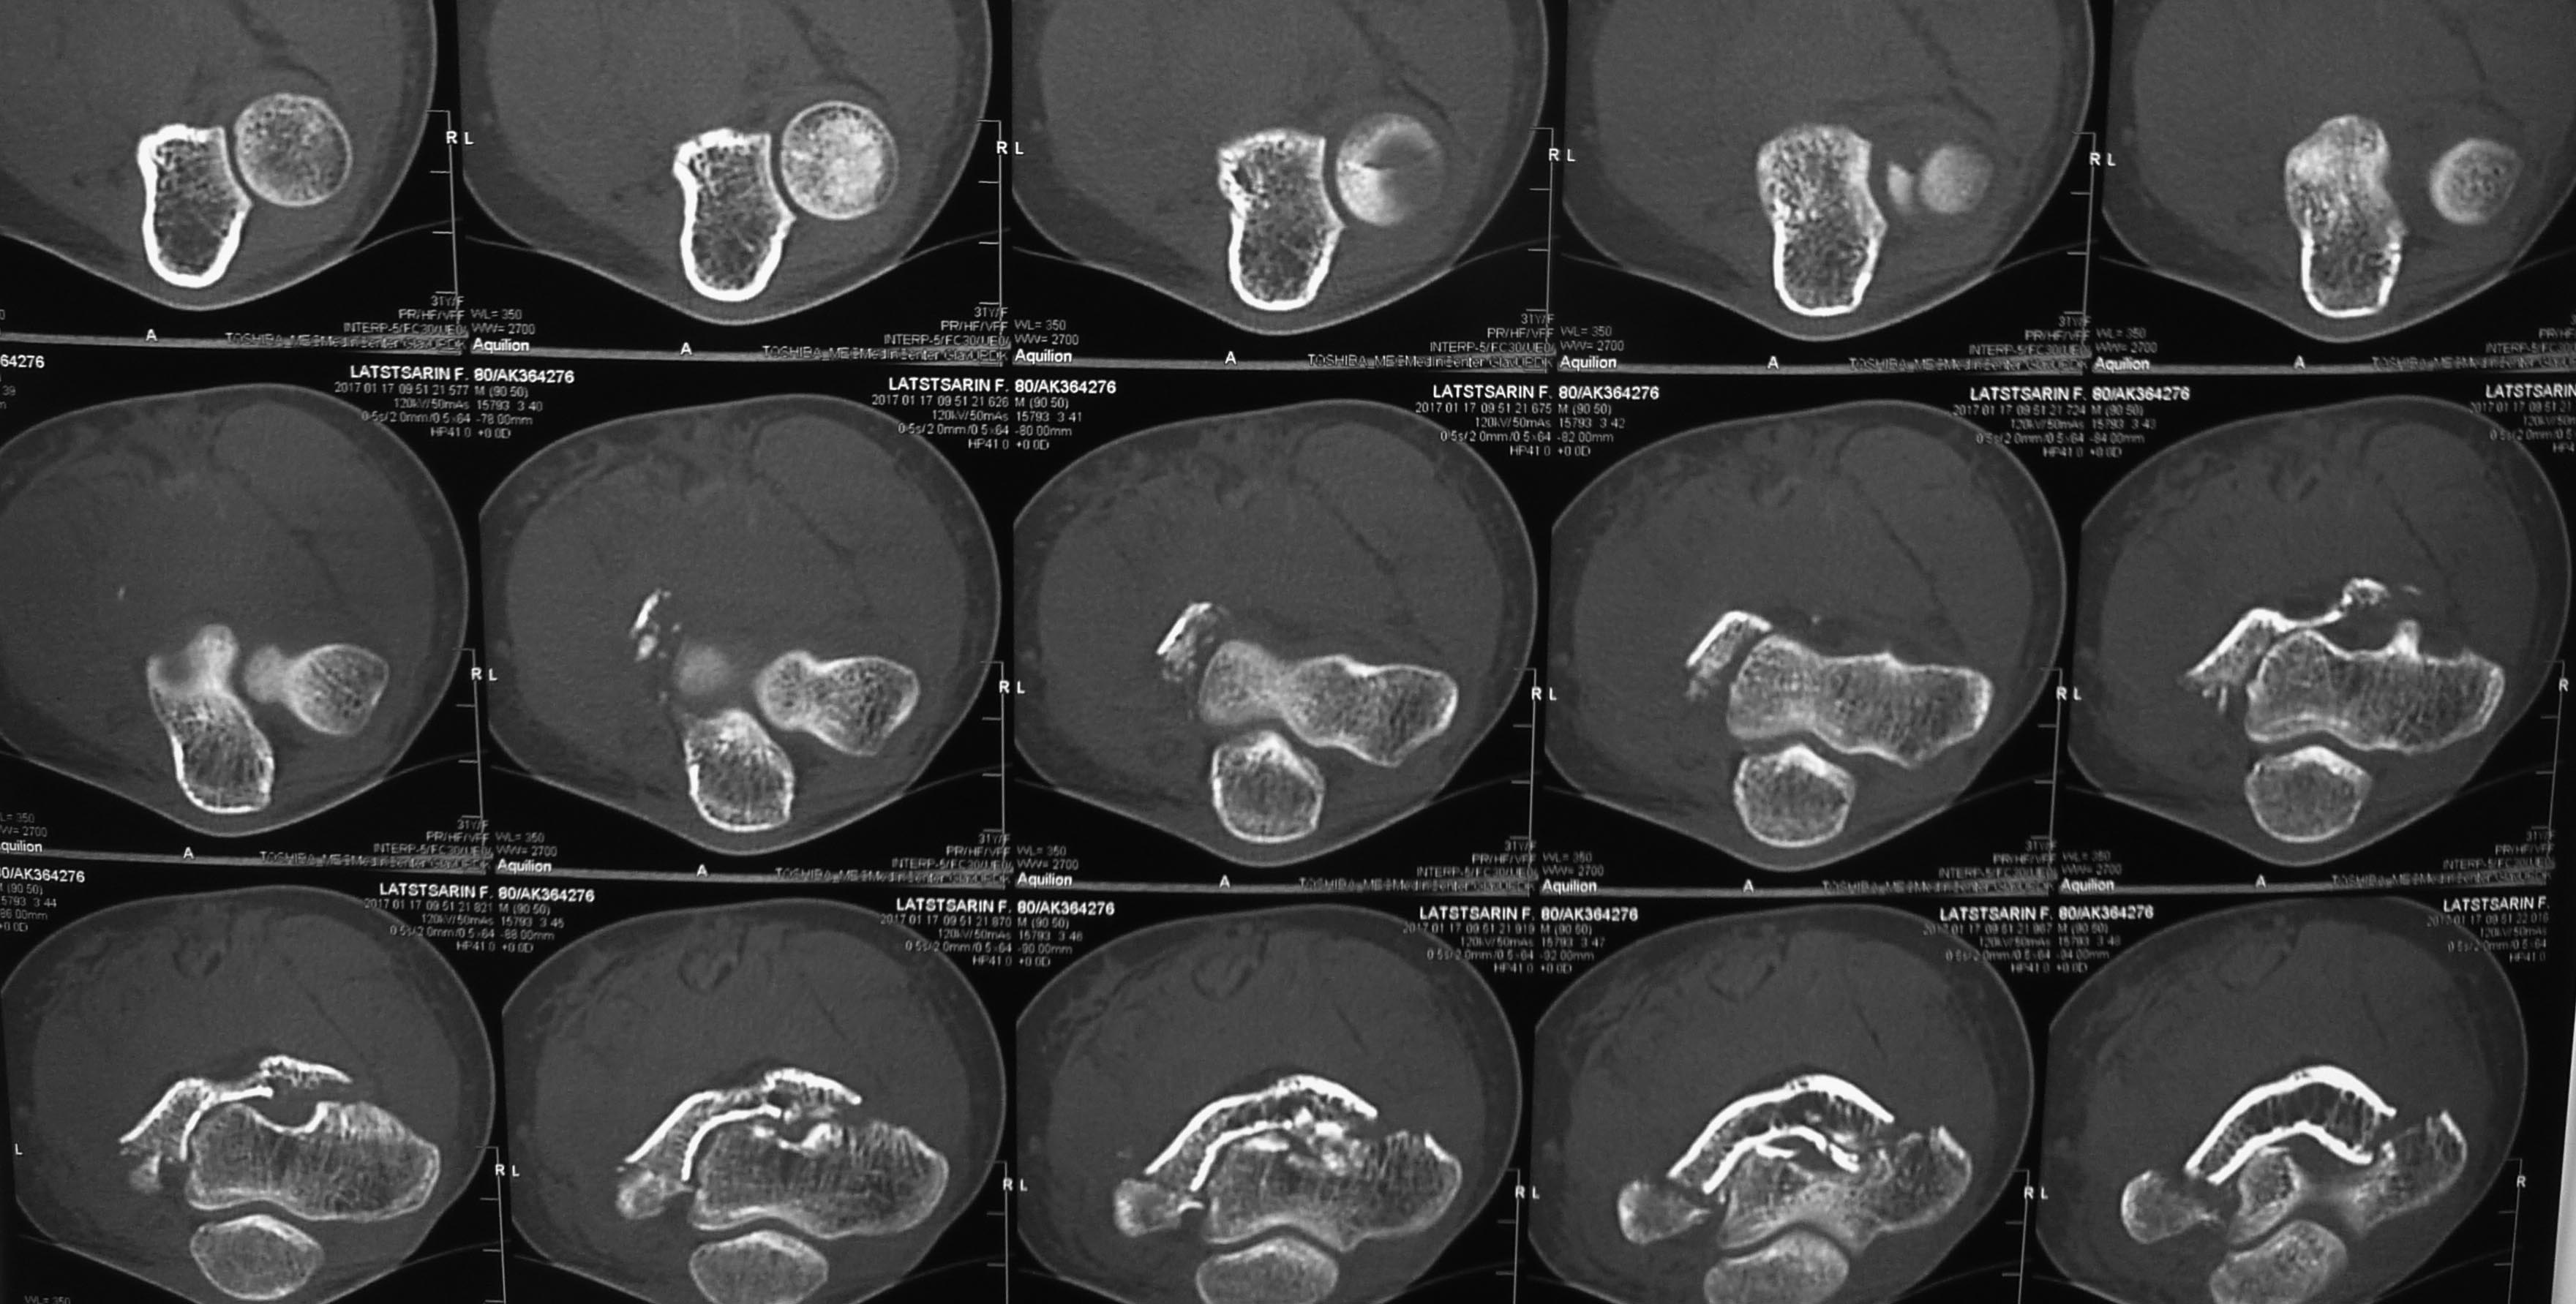

Перелом плечевой и головки лучевой костей (и немного локтевой)

Травма менее суток назад. Пациентке 35 лет. Сосудистых и неврологических расстройств конечности нет.

Вопрос: обязателен ли в данном случае остеосинтез головки луча?